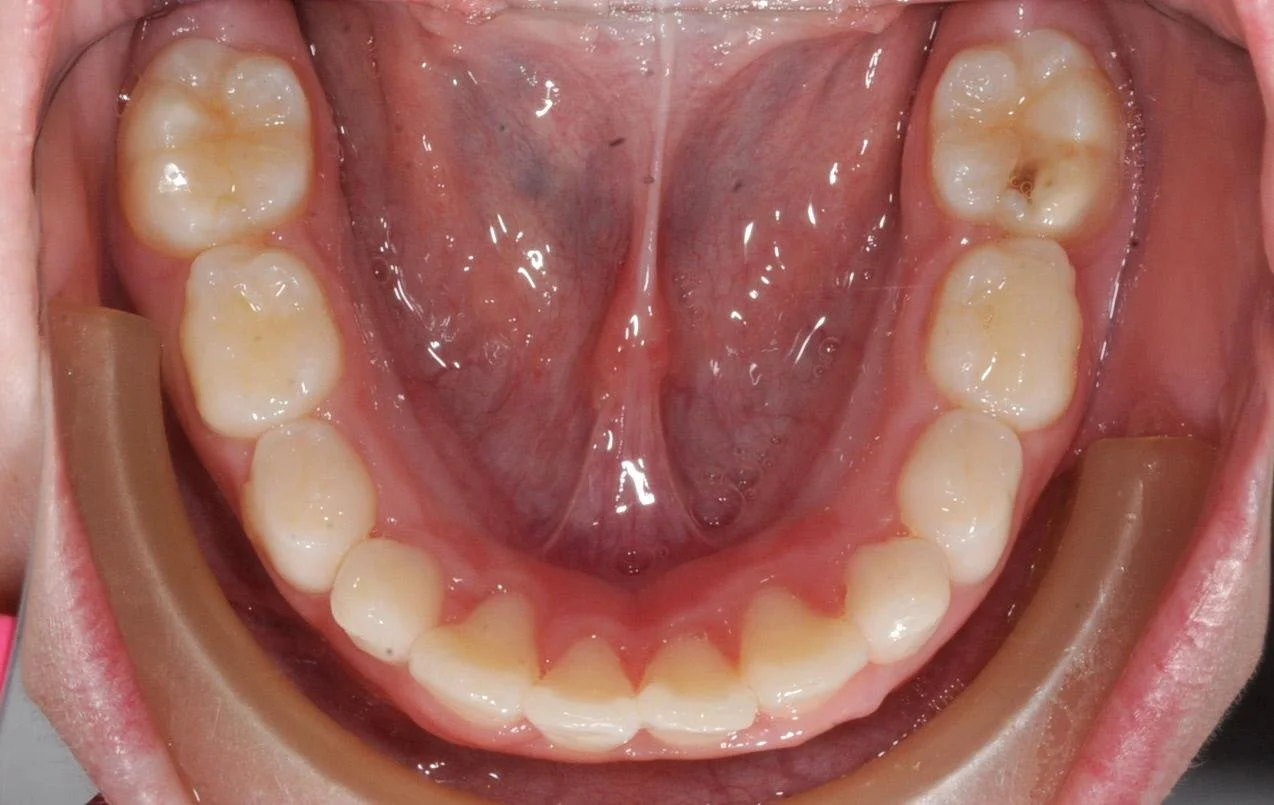

Mixed Dentition

This young patient presented with an early mixed dentition—all baby teeth on the top and two permanent teeth beginning to emerge on the bottom.

Right away, we observed severe crowding in the lower jaw. The permanent teeth, much larger than the primary teeth, were struggling to find space. Additionally, her bite presented a deep overlap, where her upper teeth fully covered her lower teeth when closing. This "deep bite" not only limited space for the incoming teeth but restricted her lower jaw’s natural forward development. When she smiled, only the upper arch was visible, with the upper teeth pressing down toward her lower gums. In fact, two of her lower teeth were forced sideways due to the space constraints, an early indication of misalignment that could worsen over time.